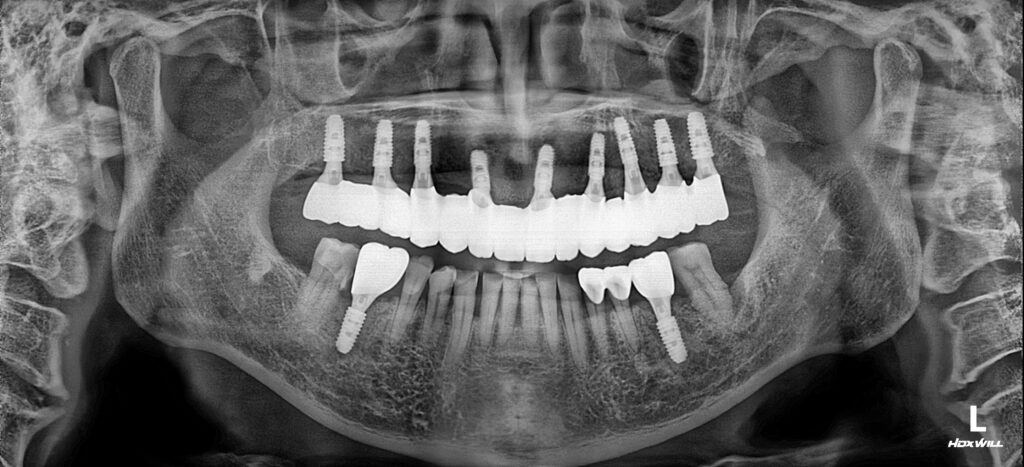

영도치과 서울화이트S치과는 상악은 전악 임플란트로, 하악은 치주질환으로 흔들리는 어금니 부위에 임플란트를 식립하여 구강기능 회복과 편안한 식사를 통해 충분한 영양섭취를 하실 수 있도록 치료계획을 수립하였습니다.

임플란트의 뿌리부분인 픽스쳐(Fixture)가 지지력을 온전히 가질 수 있는 것을 확인하고 보철물 제작까지 마무리된 모습입니다. 워낙 약해진 치조골이여서 뼈 이식을 통해 단단하게 식립해드렸습니다.